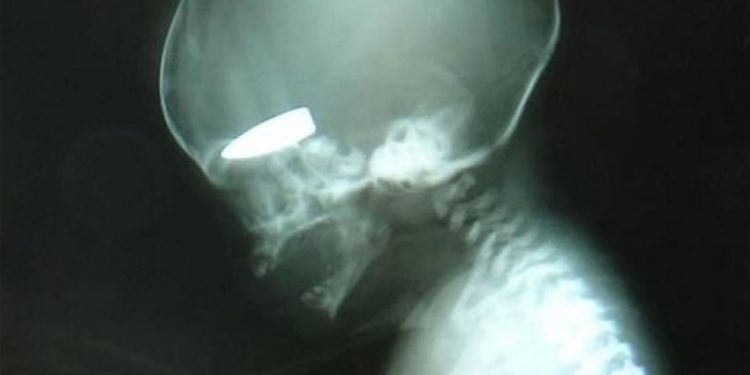

Η φωτογραφία είχε δημοσιοποιηθεί πριν από μερικές μέρες στο βρετανικό Τύπο. Υπήρχαν κάποιες επιφυλάξεις για τη γνησιότητά της σ΄ αυτό το πόλεμο προπαγάνδας που γίνεται στη Συρία. Τώρα όμως δημοσιοποιείται και το σκληρό βίντεο από βρετανό γιατρό που αποδεικνύει το αδιανόητο:

Έγκυες γυναίκες είναι στόχοι ελεύθερων σκοπευτών στη Συρία και μάλιστα “επιβραβεύονται” μ΄ αυτό με μερικά πακέτα τσιγάρα.

Σε μία μόνο ημέρα περισσότερες από έξι έγκυες γυναίκες είχαν χτυπηθεί από πυρά ελεύθερων σκοπευτών. Οι περισσότερες επιβίωσαν όχι όμως και τα έμβρυα.